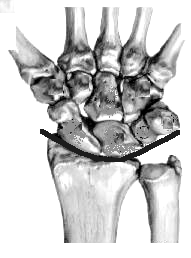

Two wrist creases on the hand's palmar (or volar) surface are landmarks for the locations of the radiocarpal and midcarpal joints.

Carpal tunnel:

The "strut" that maintains the tunnel's shape is the flexor retinaculum, also called the transverse carpal ligament or the volar carpal ligament.

This ligament connects the scaphoid and trapezium on the hand's radial side with the hamate on the ulnar side.

| The 3-D image is modified from Charles Eaton MD

The carpal tunnel contains (from radial to ulnar side):

- FCR tendon

- FPL tendon

- median nn.

- tendons of FDS and FDP

- also contains vascular structures